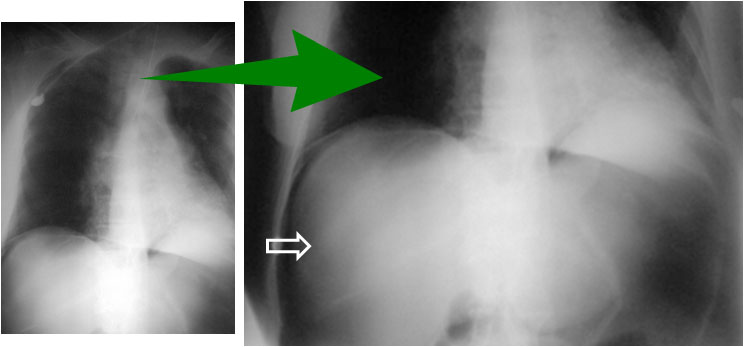

SIGNO DE LAS INSERCIONES DIAFRAGMÁTICAS

Signo de neumoperitoneo en la radiografía simple de abdomen, aunque también puede verse en la de tórax, como en este caso. El gas extraluminal dibuja las inserciones diafragmáticas derechas como dos o tres líneas curvas con densidad de partes blandas, cuyos extremos superomediales se unen en la zona del tendón central del diafragma.

A la izquierda, radiografía posteroanterior de tórax en bipedestación, que muestra un extenso neumoperitoneo bajo ambas cúpulas diafragmáticas. La imagen de la derecha es la ampliación del área subdiafragmática derecha. En ella se perfilan las inserciones diafragmáticas (flechas).

Imagen localizada de TC de abdomen en un paciente con neumoperitoneo (flechas negras). Las flechas rojas señalan las inserciones diafragmáticas.